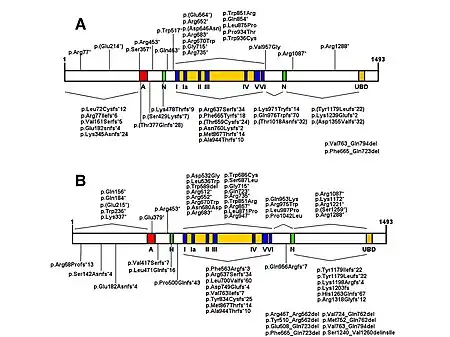

| CSB protein and domains a) Homozygous mutations are indicated, b) represents heterozygous mutations[1] | |

- Mutations in the ERCC8 (also known as CSA) gene or the ERCC6 (also known as CSB) gene are the cause of Cockayne syndrome.[8] Mutations in the ERCC6 gene mutation makes up ~70% of cases. The proteins made by these genes are involved in repairing damaged DNA via the transcription-coupled repair mechanism, particularly the DNA in active genes. DNA damage is caused by ultraviolet rays from sunlight, radiation, or free radicals in the body. A normal cell can repair DNA damage before it accumulates. If either the ERCC6 or the ERCC8 gene is altered (as in Cockayne Syndrome), DNA damage encountered during transcription isn't repaired, causing RNA polymerase to stall at that location, interfering with gene expression. As the unrepaired DNA damage accumulates, progressively more active gene expression is impeded, leading to malfunctioning cells or cell death, which likely contributes to the signs of Cockayne Syndrome such as premature aging and neuronal hypomyelination.[8]